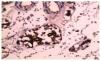

Se realiza entonces nefrectomía derecha, sin complicaciones durante la cirugía o después de la misma, llamando la atención el reporte de patología número 1735-12: "Se recibió pieza patológica identificada como riñón derecho, en donde se observa tumor de 5 x 5 cm de consistencia firme grisáceo amarillento, que ocupa desde la zona medular hasta el polo inferior; al corte y tinción de hematoxilina & eosina de 40 x 0.65: lesión neoplásica que forma túbulos, separados por un estroma fibroblástico abundante, revestidos de células pleomórficas de citoplasma abundante, eosinófilo y núcleos grandes y redondos, rodeados de una reacción desmoplásica prominente; su extensión comprende desde la médula hasta la capsula de Gerota sin rebasarla, hilio renal y ganglios linfáticos, sin infiltración neoplásica" (fig. 4).

Figura 4. Nótese la disposición tubular de la lesión con núcleos prominentes y nucléolos hipercromáticos.